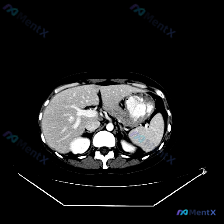

用户的疑问是“图中识别到的异常是什么?脾脏病变”,提供的是一张腹部增强CT横断面(肝门区及胃底水平)的图像描述。

- 脾脏:形态正常,密度均匀,未见明显局灶性病变。

- 肝脏:轮廓规整,肝实质密度无明显异常,肝内血管显示清晰。

- 胃:胃底有明显高密度对比剂充盈,胃壁连续,未见明确增厚或肿块。

- 其他:腹主动脉管径正常,腹膜后未见肿大淋巴结,腹腔无游离积液,骨骼肌肉未见异常。

- 总体:该层面未见确切异常占位性病变。